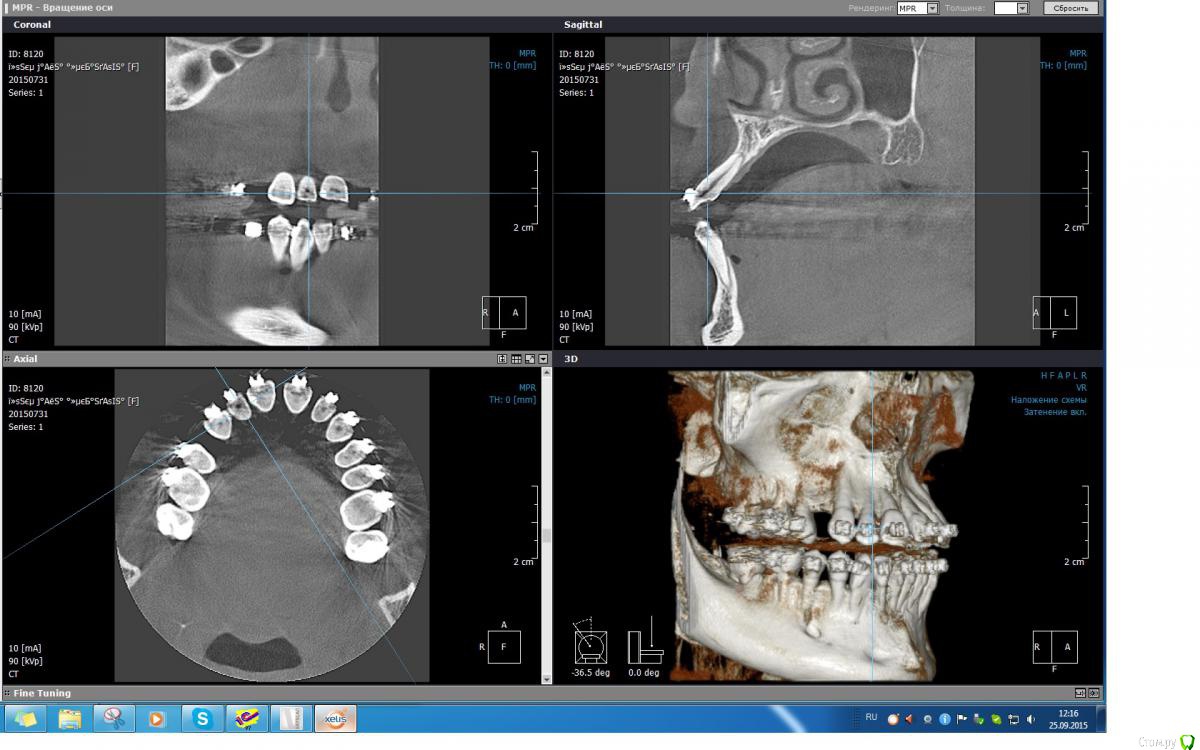

Monkey Опубликовано 22 сентября, 2015 Автор Поделиться Опубликовано 22 сентября, 2015 (изменено) А вот и зуб-курортник - 12. Изменено 22 сентября, 2015 пользователем Monkey Ссылка на комментарий

Yana guapa Опубликовано 23 сентября, 2015 Поделиться Опубликовано 23 сентября, 2015 Ох, все равно, боюсь я перфорации)) если боитесь - перестрахуйтесь и сделайте на этапе КТ Ссылка на комментарий

Monkey Опубликовано 25 сентября, 2015 Автор Поделиться Опубликовано 25 сентября, 2015 В этом-то вся печаль и состоит.... Ссылка на комментарий

Yana guapa Опубликовано 25 сентября, 2015 Поделиться Опубликовано 25 сентября, 2015 только состояние двойки беспокоит?)) меньше КТ делаешь - крепче спишь)))))) Ссылка на комментарий